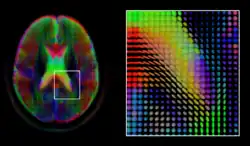

Given the principal direction of diffusion at each location in the volume, it is possible to estimate the global pathways of diffusion through a process known as tractography.[66] However, due to the relatively low resolution of diffusion MRI, many of these pathways may cross, kiss or fan at a single location. In this situation, the single principal direction of the diffusion tensor is not an appropriate model for the local diffusion distribution. The most common solution to this problem is to estimate multiple directions of local diffusion using more complex models. These include mixtures of diffusion tensors,[67] Q-ball imaging,[68] diffusion spectrum imaging [69] and fiber orientation distribution functions,[70][71] which typically require HARDI acquisition with a large number of gradient directions. As with the diffusion tensor, volumes valued with these complex models require special treatment when applying image computing methods, such as registration[72][73][74] and segmentation.[75]

When working with large cohorts of subjects, the normalization (registration) of individual subjects into a common reference frame is crucial. A body of work and tools exist to perform normalization based on anatomy (FSL, FreeSurfer, SPM). Alignment taking spatial variability across subjects into account is a more recent line of work. Examples are the alignment of the cortex based on fMRI signal correlation,[84] the alignment based on the global functional connectivity structure both in task-, or resting state data,[85] and the alignment based on stimulus specific activation profiles of individual voxels.[86]